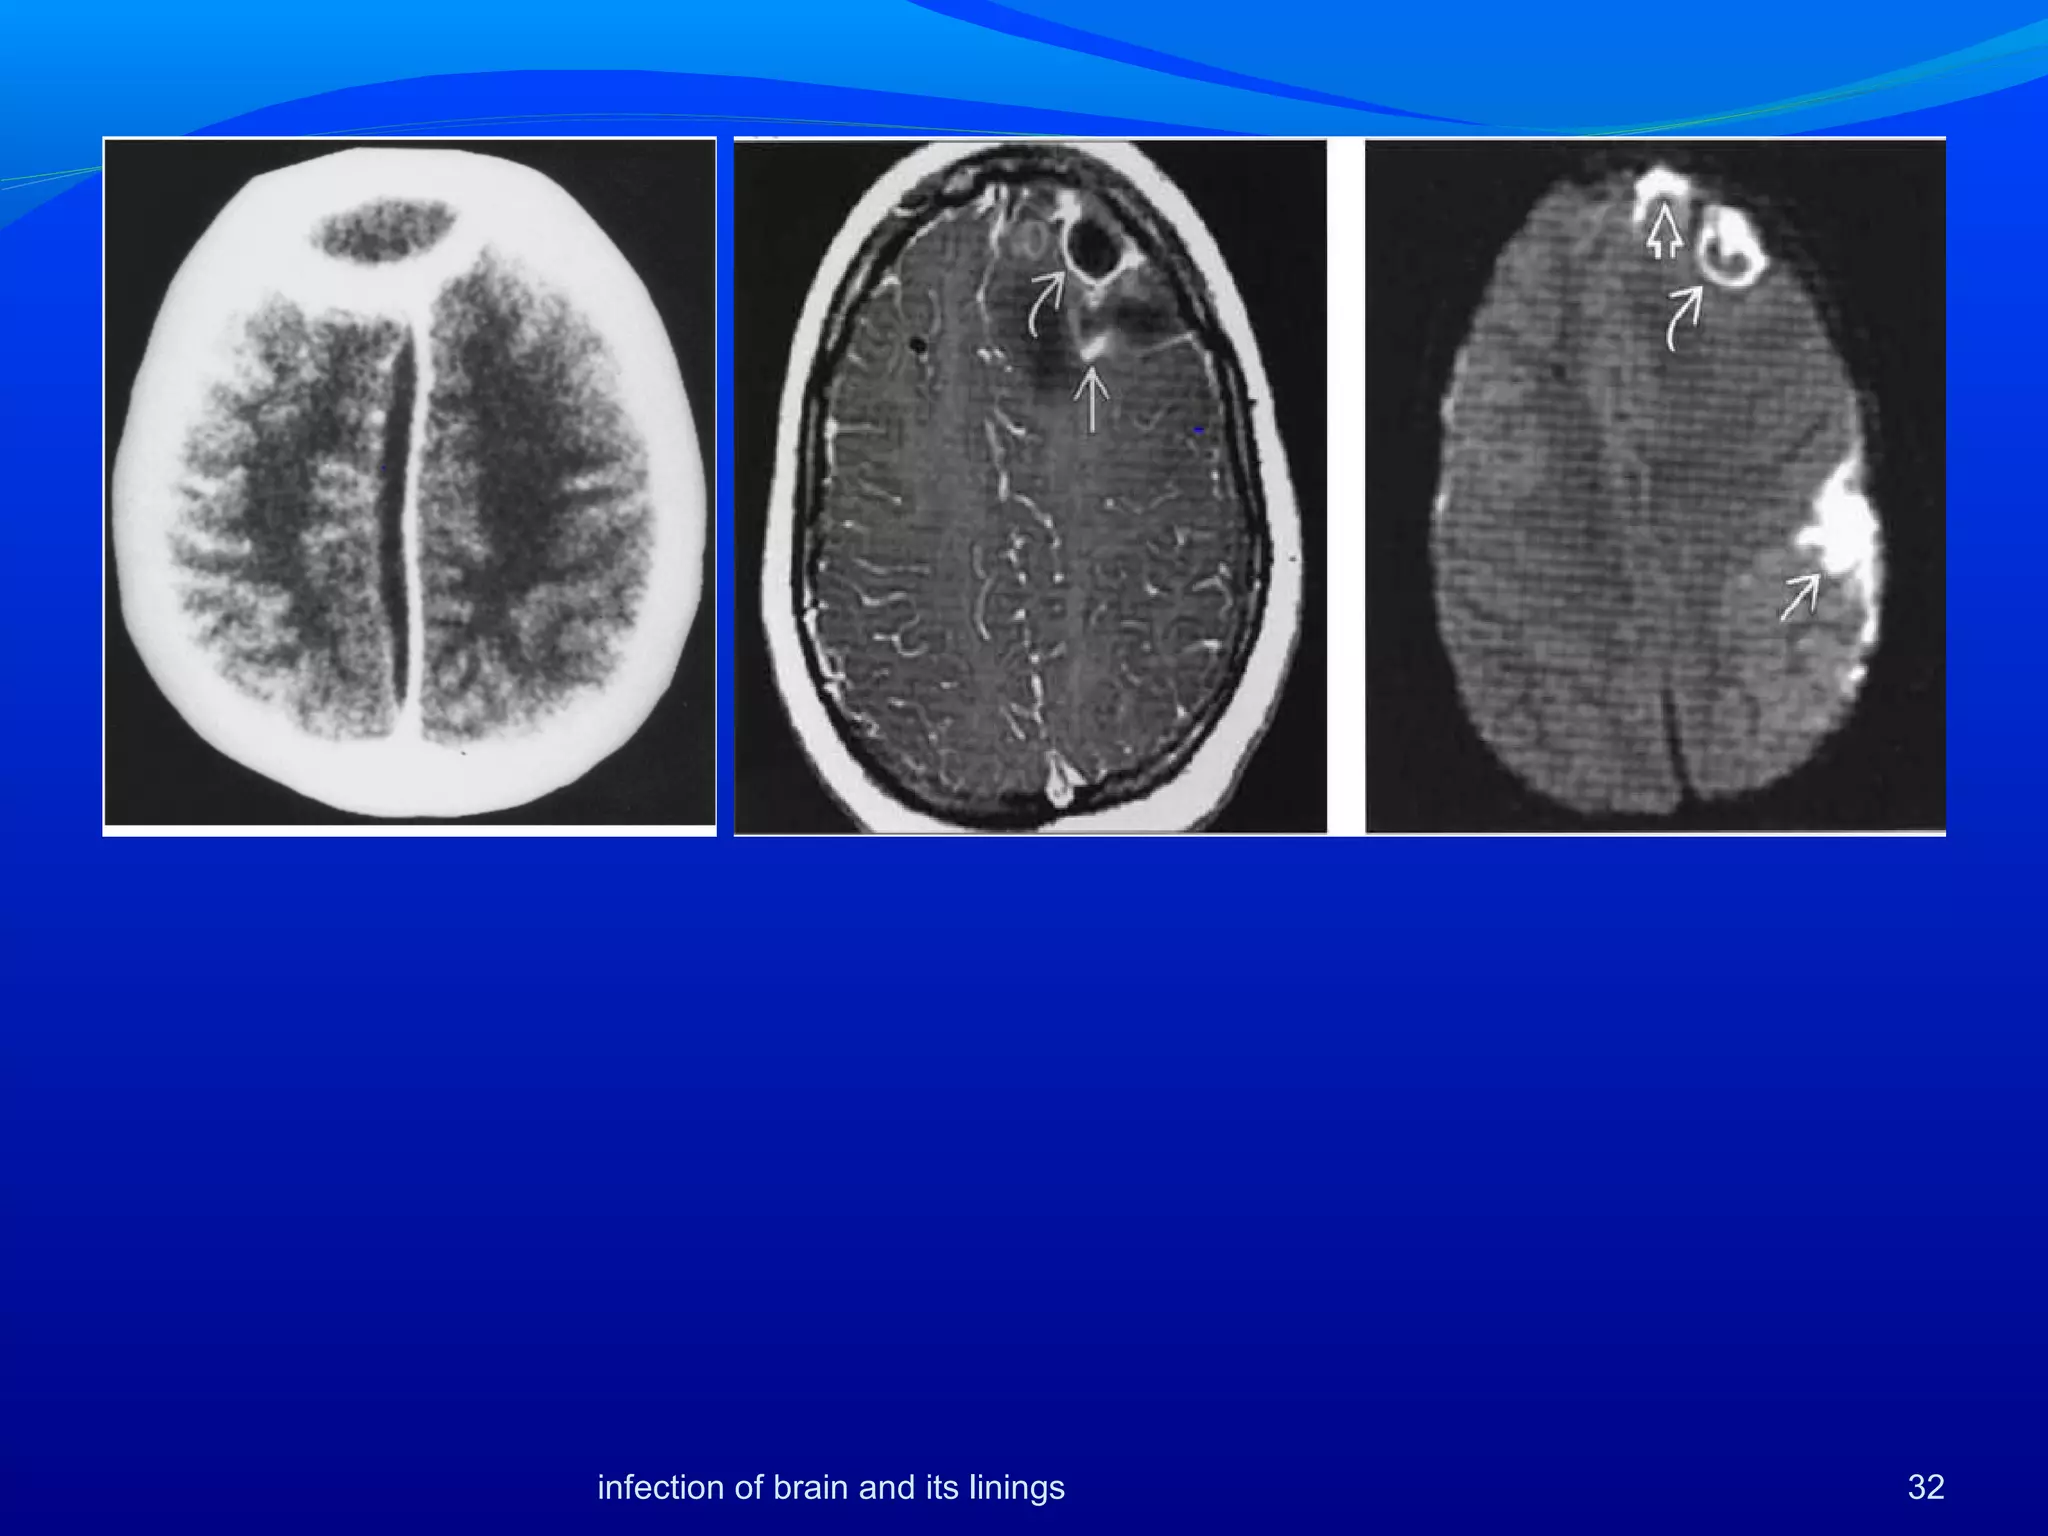

• 67.

infection of brainand its linings 67 co-infection

• 66.

Neurocysticercosis and JE asymmetricwith lateralization to the side of the brain having maximum NCC or a cyst with edema. were more florid with significantly higher amount of abnormal CT scans and more abnormal MR imaging more common in children. Altered immune status in co-infections were suggested by significantly lowered levels of JE IgM. 66infection of brain and its linings